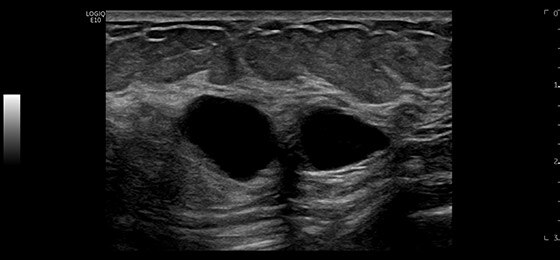

Breast Cysts, ML6-15-D